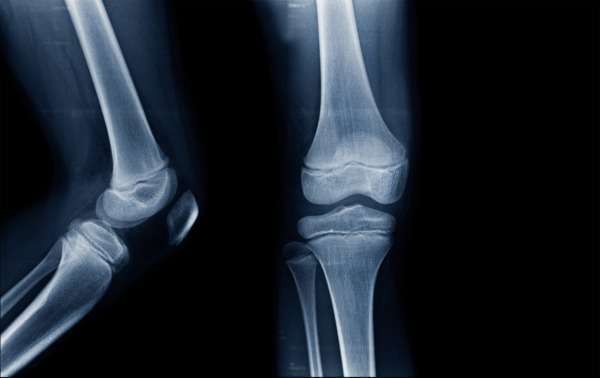

Typically found within joints, hyaline cartilage is low-friction, wear-resistant and super flexible. This strong, rubbery tissue is specifically designed to bear and distribute weight where certain bones meet.

Without this type of cartilage, we’d be rendered immobile. Fibro cartilage is super tough and inflexible. It is found at two locations in the human body: the knees and between the vertebrae.

- Cartilage cushions our skeletal system from impact and, as such, assists in the prevention of injury.

- Osteoarthritis occurs when the cartilage in joints breaks down and becomes brittle, causing pain when performing certain movements.